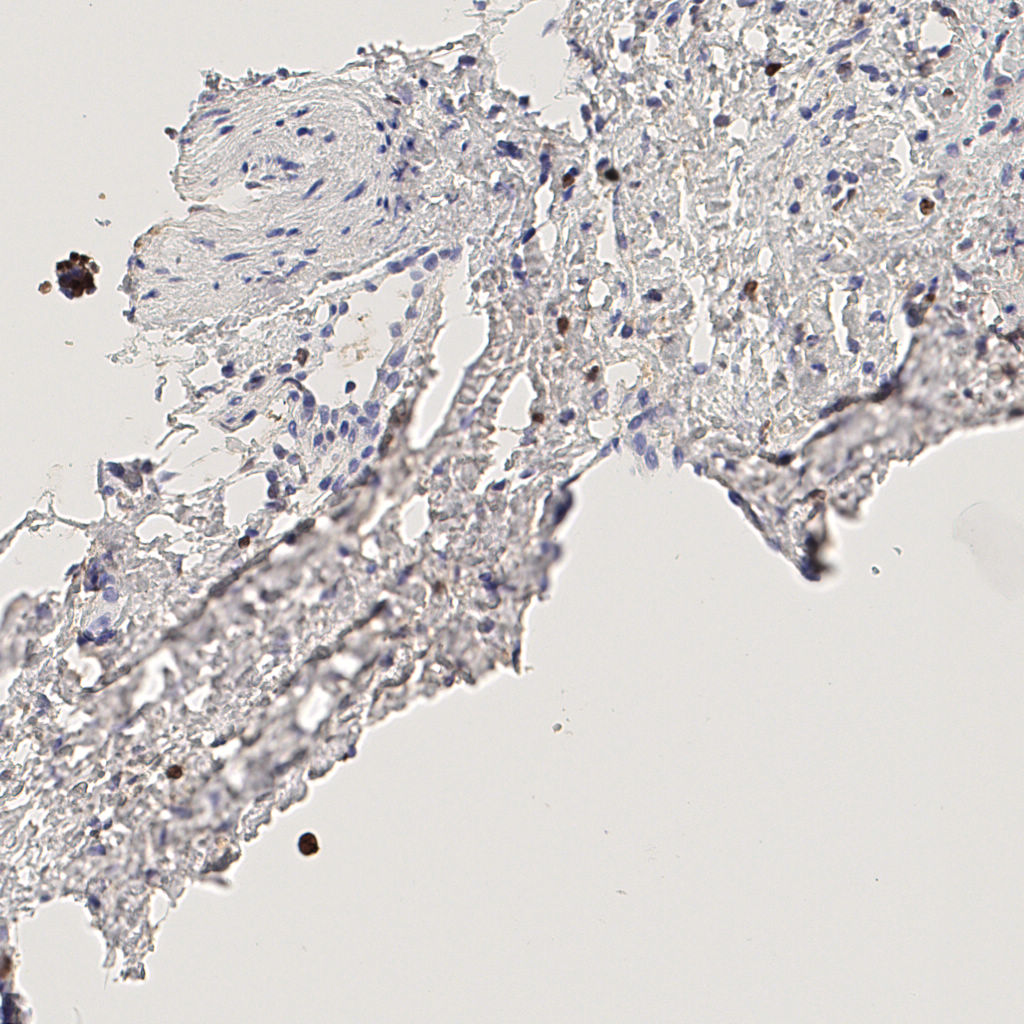

7.85%

Ki67 指数

阴 1104 阳 94

H255858-KI-67.ndpi